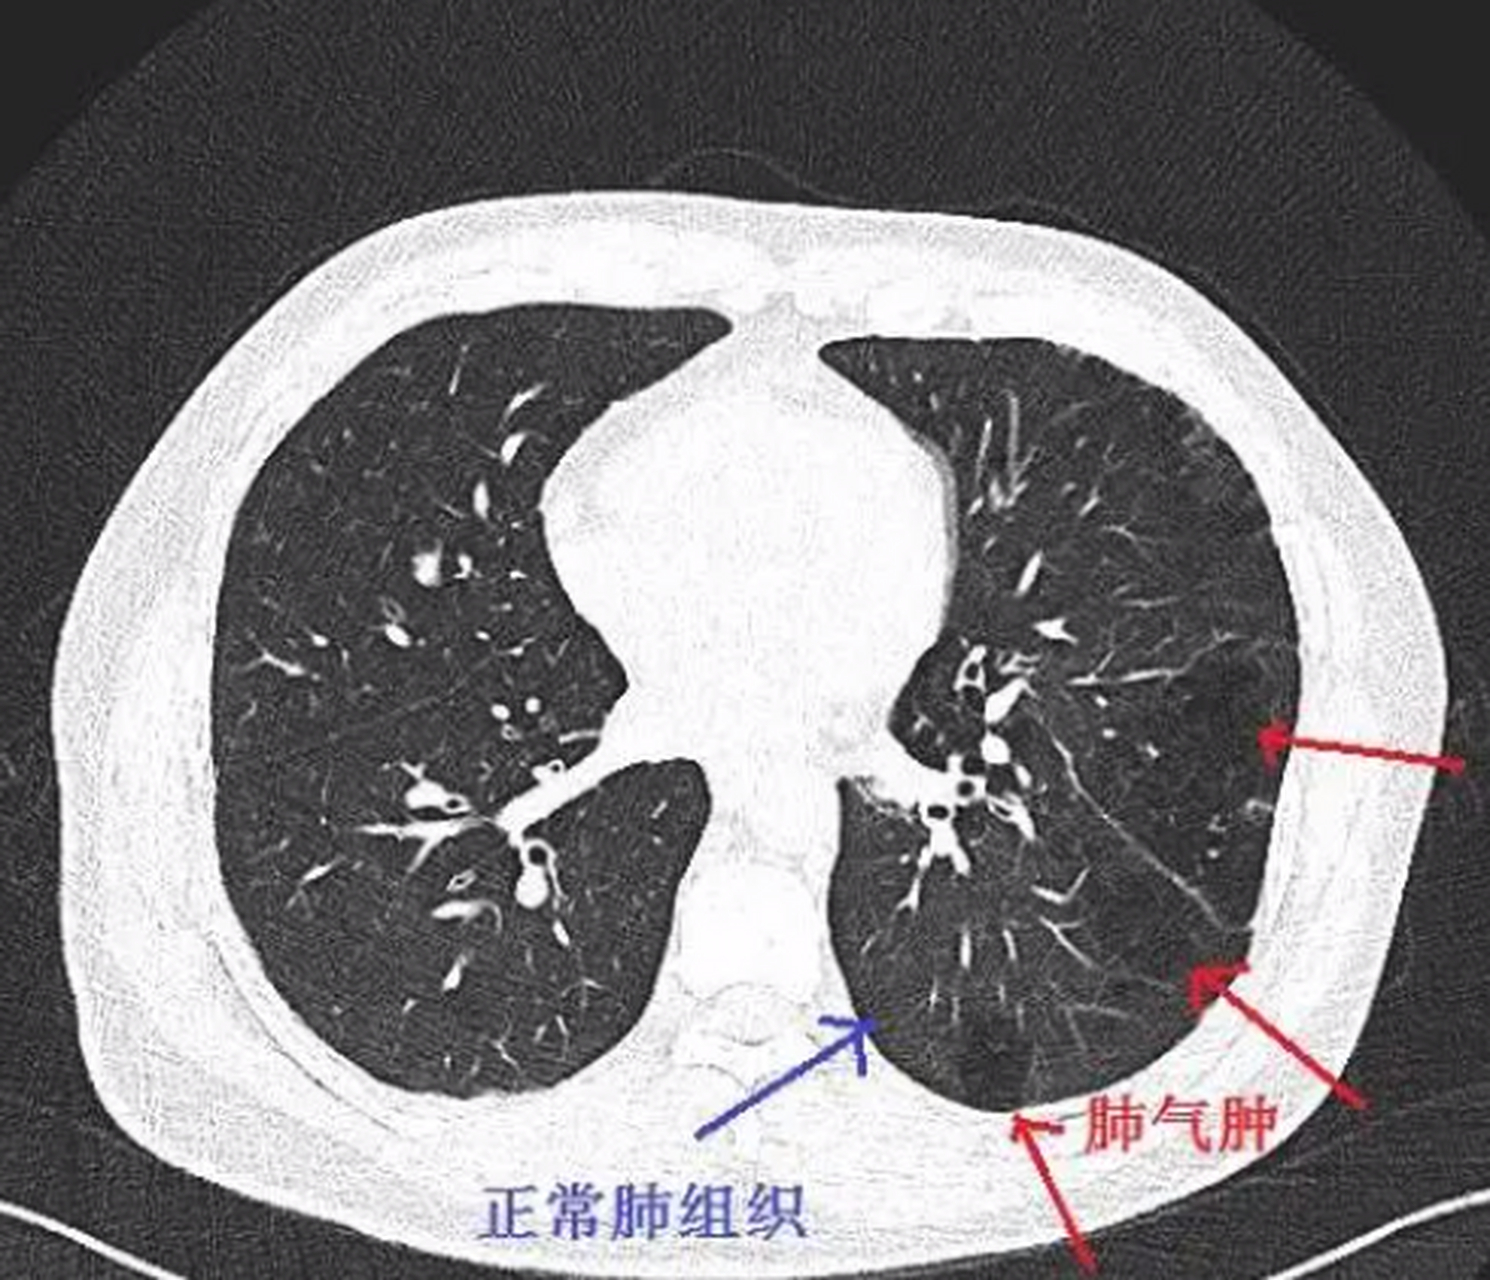

肺气肿

肺气肿的影像诊断_全小叶